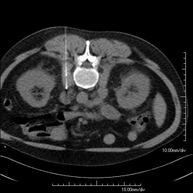

Prova diagnòstica que consisteix en l'estudi de l'abdomen d'alta definició anatòmica (fetge, vesícula biliar, via biliar, pàncrees, melsa, estómac, intestins, ronyons, estructures vasculars, bufeta, úter i ovaris, etc.) mitjançant l'ús d'un equip de TC (Tomografia Computeritzada). Aquestes imatges s'estudien posteriorment en una estació de treball que permet obtenir reconstruccions bidimensionals en diferents plànols de l'espai i també reconstruccions 3D (volumètriques). La majoria d'estudis requereixen l'ús de contrast iodat per millorar la definició de les imatges. - TC Pelvis

Prova diagnòstica que consisteix en obtenir imatges bi i tridimensionals de la pelvis d'alta definició anatòmica (estructures òssies, estructures vasculars, bufeta, úter i ovaris, pròstata i vesícules seminals, urèters, etc.) mitjançant l'ús d'un equip de TC (Tomografia Computeritzada). La majoria d'estudis requereixen l'ús de contrast iodat. - TC Abdominopèlvic

Prova diagnòstica que consisteix en obtenir imatges bi i tridimensionals de l'abdomen d'alta definició anatòmica (estructures òssies, estructures vasculars, fetge, pàncrees, vesícula biliar, ronyons, glàndules suprarenals, melsa, intestí prim i gros, bufeta, úter i ovaris, pròstata i vesícules seminals, urèters, etc.) mitjançant l'ús d'un equip de TC (Tomografia Computeritzada). La majoria d'estudis requereixen l'ús de contrast iodat. - TC Fetge